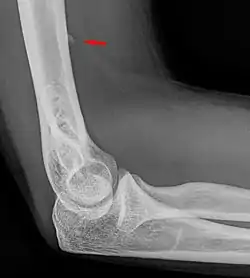

![]() Small supracondylar process seen on a lateral radiograph of the elbow | |